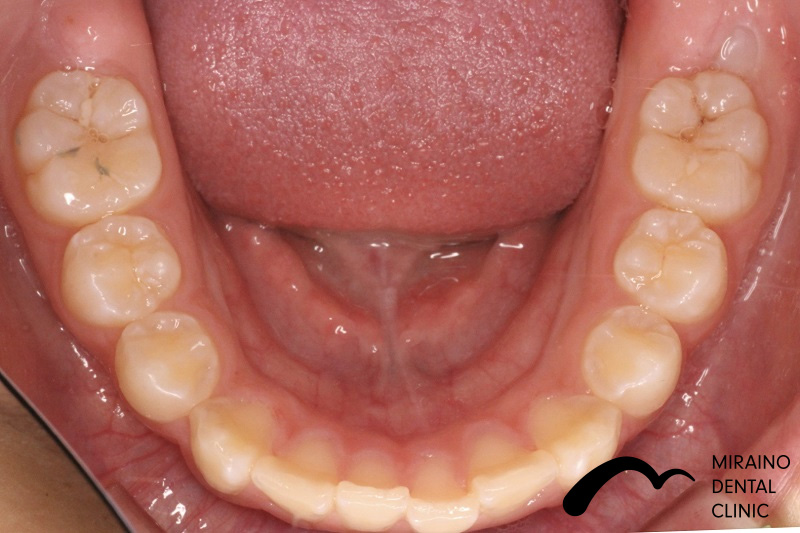

叢生(ガチャガチャ・ガチャ歯)①

| 施術名 | マウスピース矯正(インビザライン) |

| 施術の内容 | 歯科矯正でも目立ちにくい新しい矯正方法です。 透明に近いマウスピース型の矯正装置(アライナー)のため、歯に装着しても目立つことなく歯並びを矯正することが出来ます。 また、一人ひとりの合わせて矯正装置を作製いたします |

| 治療費 | インビザライン990,000円 |

| 考えられるリスク、副作用 | 疼痛・咬合時痛を生じる事があります。 時間経過とともに治ります。 |

| 考えられるリスク、副作用[矯正] | 継続使用により緩んだり、外れやすくなる事があります。 割れたり壊れたりする事があります。 諸々の事情により、治療期間が当初よりも伸びる事があります。 所定の装着時間22時間を守って頂けない場合、治療計画どおりに治らない可能性があります。 歯が動く際に、痛みが出る事があります。 矯正期間中は虫歯や歯周病のリスクが高まりますので、しっかりとしたケアが必要です。 歯の移動に伴う歯肉退縮や歯根吸収が起こる事があります。 インビザライン・システム(invisalignR)は、アメリカのアラインテクノロジー社より提供されている、カスタムメイドの矯正装置ならびに、これを用いた治療システムを指します。 インビザラインを用いた治療は保険適用外の自由診療となります。 厚労省の認可(医薬品医療機器等法上の承認)は得ていないため、まだ明らかになっていないリスクが存在する可能性があることをご了承ください。 |

| 全て | 必ずしもご希望通りの見た目にならない事があります。 |